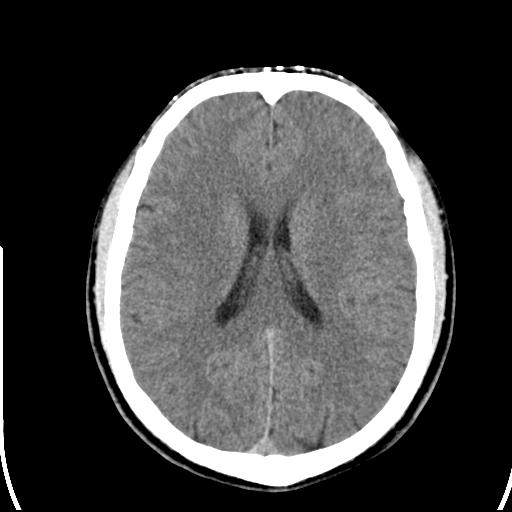

头皮下高密度结节影???临床上在老年男性比较常见。大家看看是什么?成因是? 本例患者,男性,51岁。外伤来诊。无染发史及发根植入史。